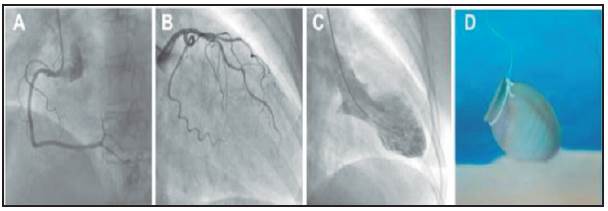

A 58-year-old female patient who only had a history of controlled arterial hypertension and depression (which was currently being treated) presented to the emergency room with a complaint of oppressive retrosternal chest pain beginning one hour before, radiating to the left arm and with an intensity of 10/10 on the analog pain scale; diapho resis; dyspnea; nausea and a feeling of impending doom. The symptoms were triggered by a stressful emotional event. She went to the emergency room where clinical assessment and paraclinical tests documented a possible acute coronary syndrome, such as acute myocardial infarc tion with ST elevation. The admission electrocardiogram showed a sinus rhythm with a normal QRS axis, elevated ST on V5-V6, and an inverted T wave on precordial V4 and V5 with signs suggestive of left ventricular overload; the remaining leads were within normal limits (Figure 1). The chest x-ray showed a slightly increased cardiac silhouette with no evidence of parenchymal infiltrates or pulmonary congestion. The complete blood count and other blood chemistry studies were within normal limits. The cardiac biomarkers showed increased troponin I at 0.283 ng/dL with a 99th percentile reference value of 0.014 ng/ dL. Thus, it was initially considered to be an acute coro nary syndrome of the acute myocardial infarction with ST elevation variety. Since the emergency room was at a quaternary level institution, the patient was transferred in under 120 minutes to the hemodynamics department and a percutaneous coronary intervention was ordered. The study showed: no obstruction of the coronary arteries or their branches, with a left ventriculography suggestive of latero-apical akinesia and ventricular ballooning with a diminished ejection fraction of 40%, suggesting takotsubo (Figure 2). An echocardiogram was performed in the cath lab recovery room which described: a normal-sized left ventricle, without wall hypertrophy, moderately decreased systolic function due to impaired contractility secondary to akinesia of the apex and the apical segments of all the walls, with an estimated ejection fraction of 35% with no evidence of thrombi or intra-chamber masses. The right ventricle had preserved systolic function and a normal valvular plane without pulmonary hypertension.